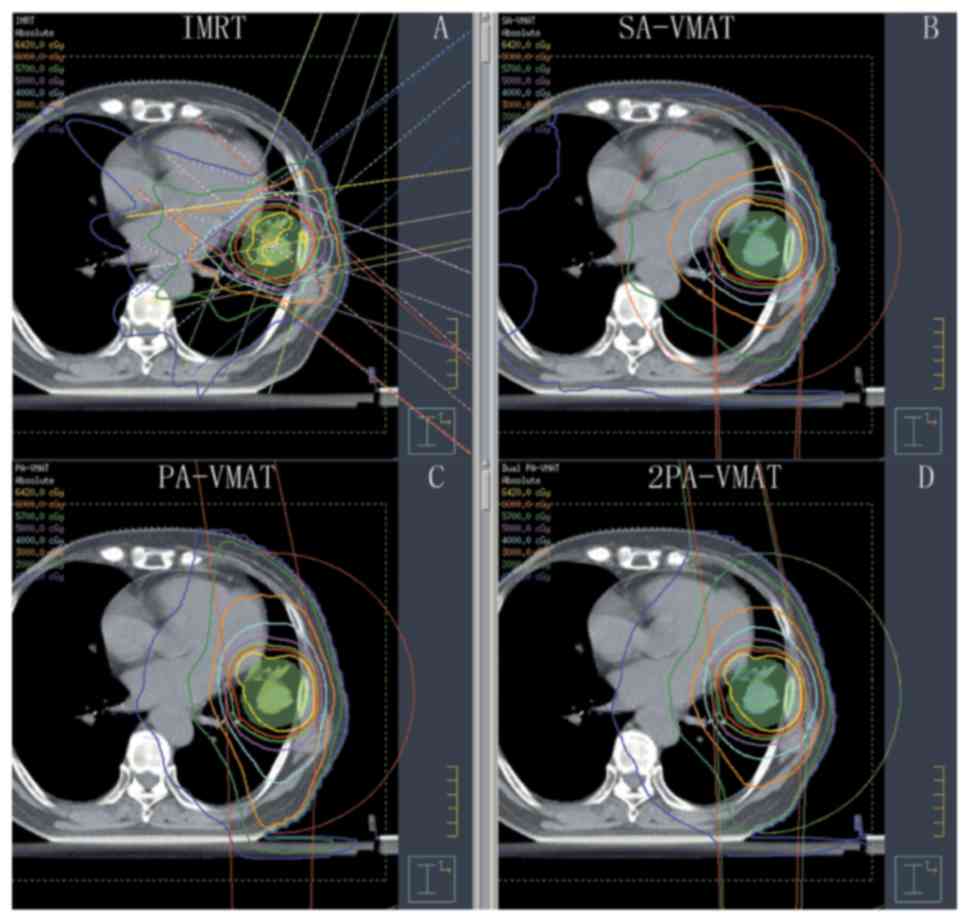

Fig. 1 illustrates the dose-volume histogram (DVH) and dose distributions of IMRT and VMAT plans of a patient with peripheral lung cancer. Figs. 2 and 3 illustrate the CI, HI and organ at risk (OAR) dosage of each patient. The average delivery times for IMRT plans and VMAT plans were 10.5 and 6.1 min respectively. VMAT plans generated larger numbers of MU compared to IMRT.

Figure 1.

Isodose curves of IMRT plan and 2PA-VMAT plan in peripheral lung cancer. (A) Isodose curves of IMRT plan. (B) Isodose curves of SA-VMAT plan. (C) Isodose curves of PA-VMAT plan. (D) Isodose curves of 2PA-VMAT plan. In peripheral lung cancer, both IMRT plan and VMAT plan exhibited satisfying prescribed tumor target coverage and OAR sparing. However, 2PA-VMAT displayed improved PTV coverage compared with IMRT. 2PA-VMAT exhibited better sparing of spinal cord, lung-all, and lung-contralateral compared with IMRT, while IMRT exhibited better heart and lung-ipsilateral sparing compared with 2PA-VMAT. IMRT had better dose conformity and homogeneity. IMRT, intensity-modulated radiation therapy; VMAT, volumetric modulated arc therapy; 2PA, double partial arc; PA, partial arc; SA, single arc; OAR, organs-at-risk.

Table II illustrated the dosage difference between VMAT and IMRT plans in peripheral lung cancer. In peripheral lung cancer, there was no significant difference of CI and HI of PTV among IMRT, SA-VMAT, PA-VMAT, and 2PA-VMAT plans (Figs. 1 and 2). The target area is far away from the spinal cord and heart, therefore the received dose of the spinal cord and heart were low; the IMRT plan achieved superior sparing of spinal cord compared with the VMAT plans, and the radiation dose of the spinal cord was the highest in the SA-VMAT plan. IMRT plans exhibited significantly improved sparing of V20, V30 of total lungs and Dmean, V30 of ipsilateral lung compared with SA-VMAT, PA-VMAT and 2PA-VMAT plans. PA-VMAT and 2PA-VMAT exhibited significantly better Dmean, V5 (%), V10 (%) of lung-contralateral compared with the IMRT plan. V5 (%) of lung-all of SA-VMAT was higher compared with PA-VMAT. V5 (%) of lung-all of IMRT plan was higher compared with SA-, PA- and 2PA-VMAT; V20, V30 (%) of lung-all of SA-, PA-, 2PA-VMAT were higher compared with IMRT. V5 (%) of lung-ipsilateral of IMRT was higher compared with SA-, PA-, 2PA-VMAT. IMRT plans also exhibited significantly improved sparing of Dmean of contralateral lung than PA- and 2PA-VMAT plans (Fig. 3).